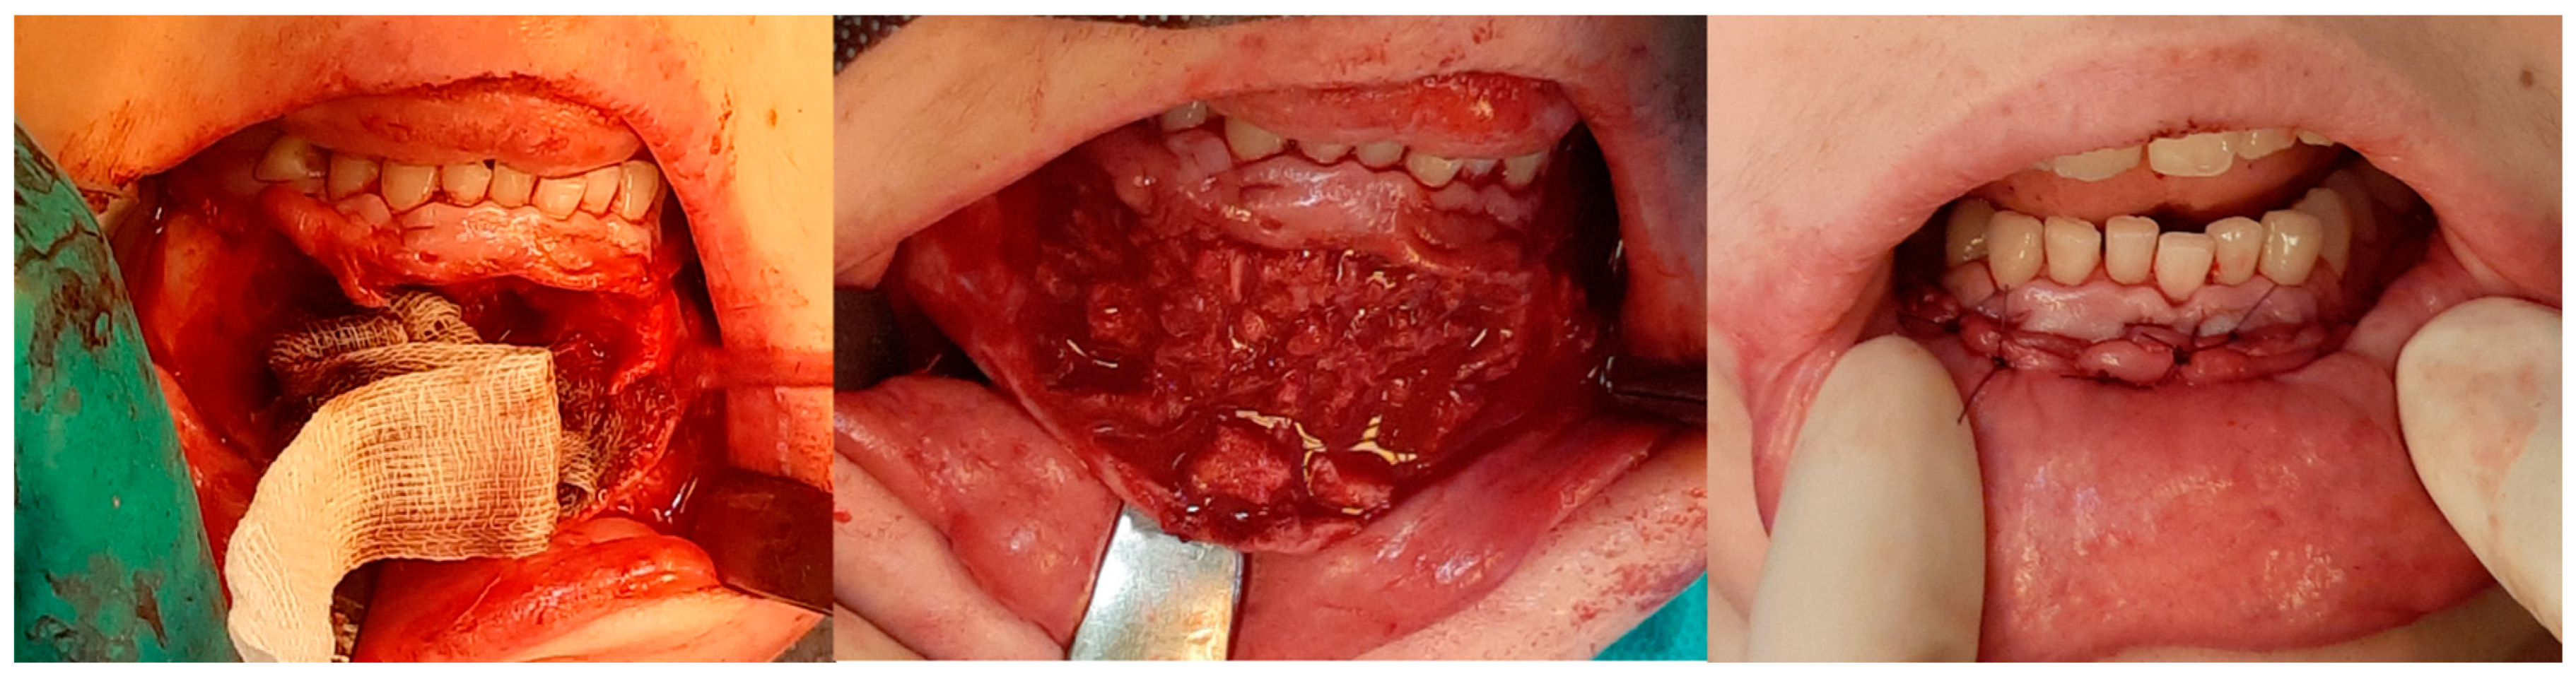

3.2. Injections